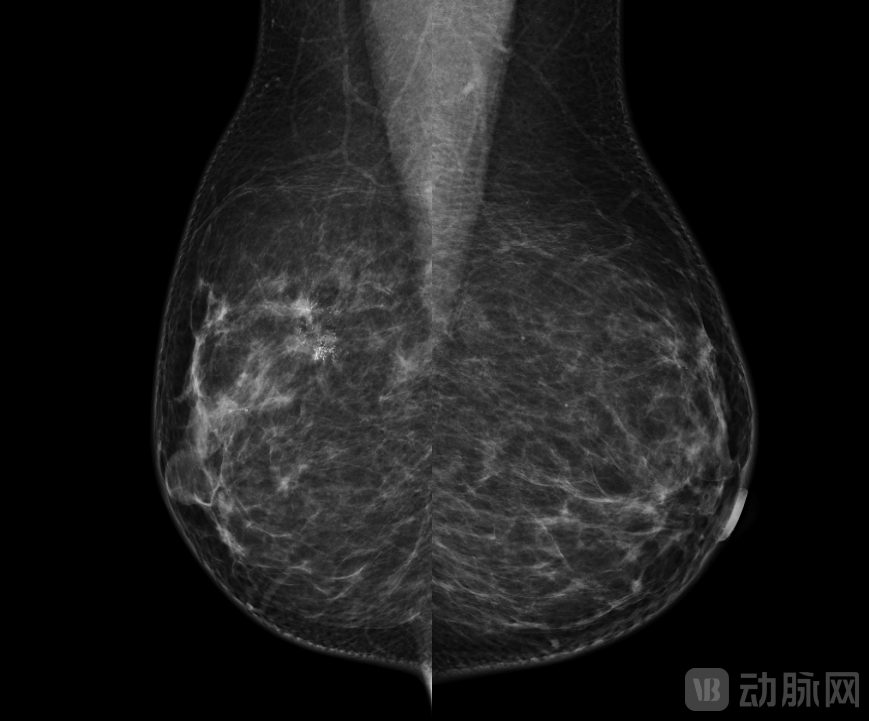

帧观德芯“清照”乳腺机及相关临床图像

乳房X线摄影:典型恶性肿块伴钙化